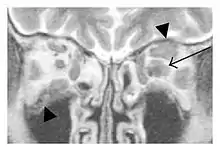

The extent of inflammation that can occur in IgG4-ROD is well demonstrated on magnetic resonance imaging (MRI).

Infraorbital nerve enlargement (IONE) is considered to be a particularly suspicious sign of IgG4-ROD, but seems to occur only when inflammation is in direct contact with the infraorbital canal.[10] IONE is defined as the infraorbital nerve diameter being greater than the optic nerve diameter in the coronal plane.

Enlargements in the left inferior rectus muscle and infraorbital nerve (arrow) in a 65-year-old man with a serum IgG4 of 404 mg/dL.[1] (T2-weighted MRI)